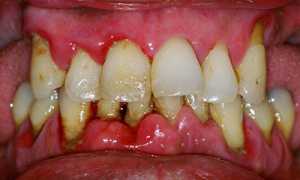

- Пародонтит средней или тяжёлой стадии. В этом случае инфекция попадает в пульпу через корневую систему либо соединительную ткань.

Периодонтит и его определение в стоматологии

Гнойный воспалительный процесс у верхушки корня. Токсины и микроорганизмы проникают в периодонтальное пространство, и инфекция стремительно прогрессирует в тканях периодонта.